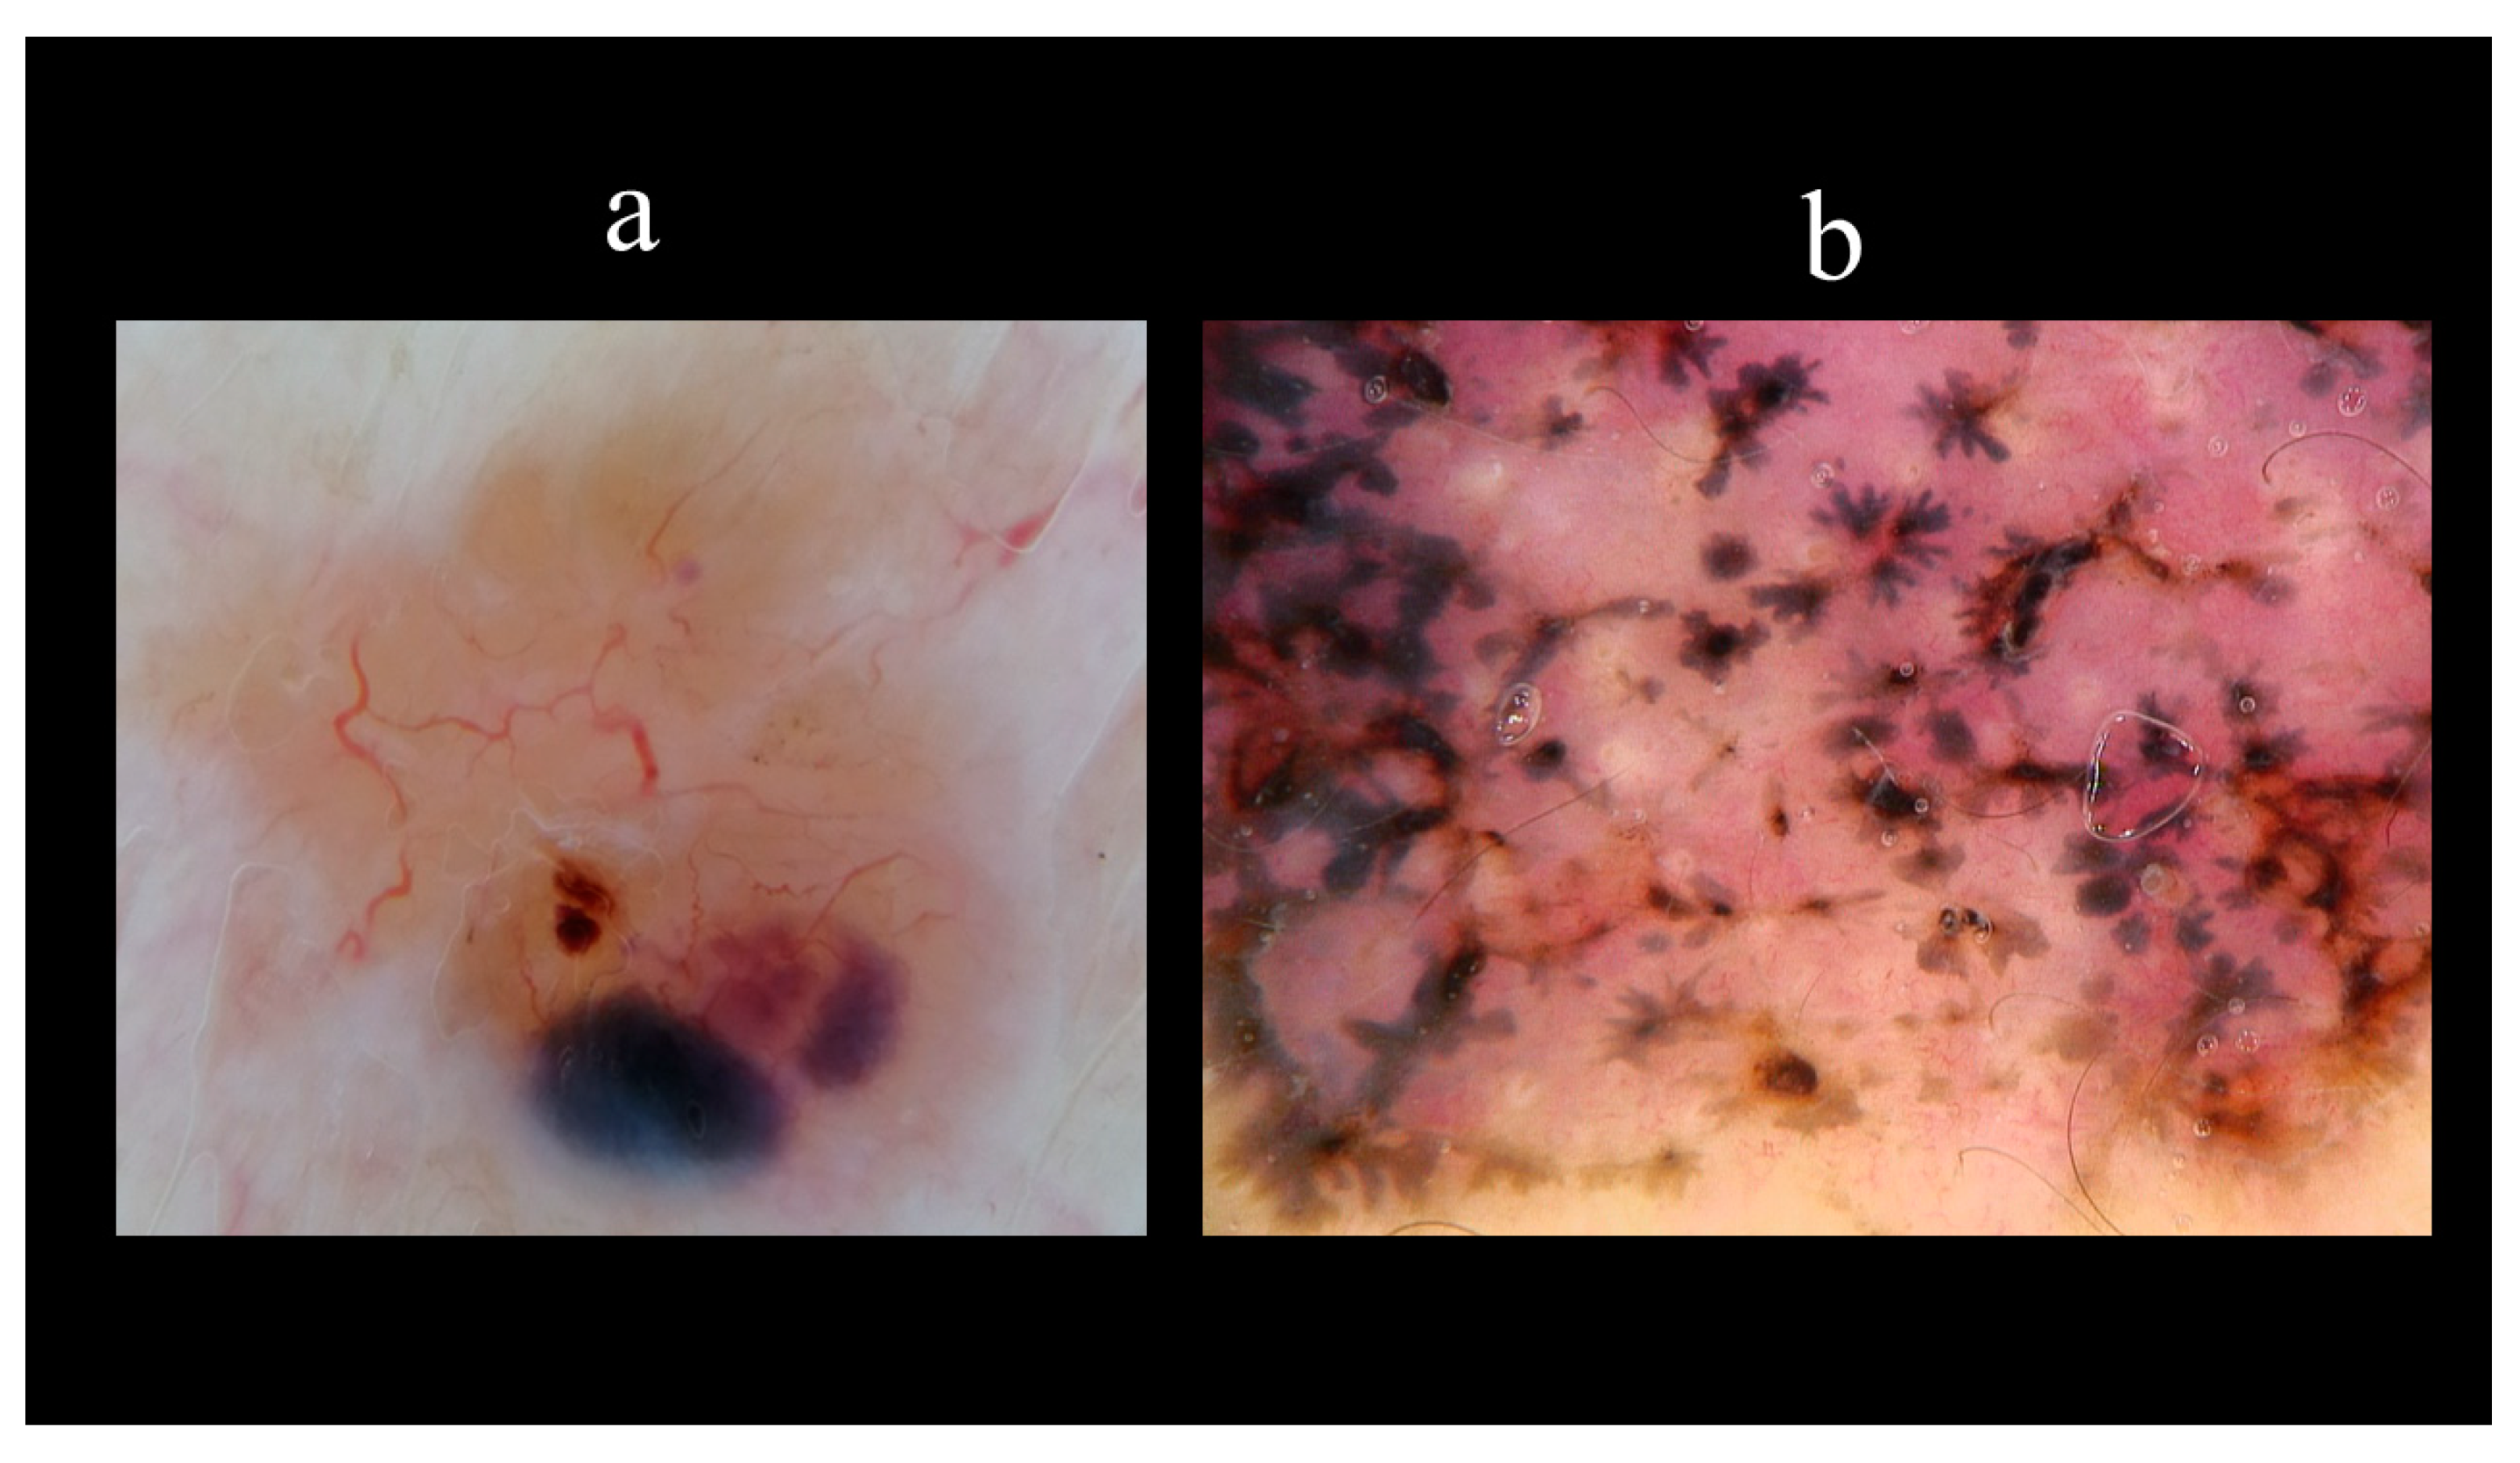

5. Dermoscopy